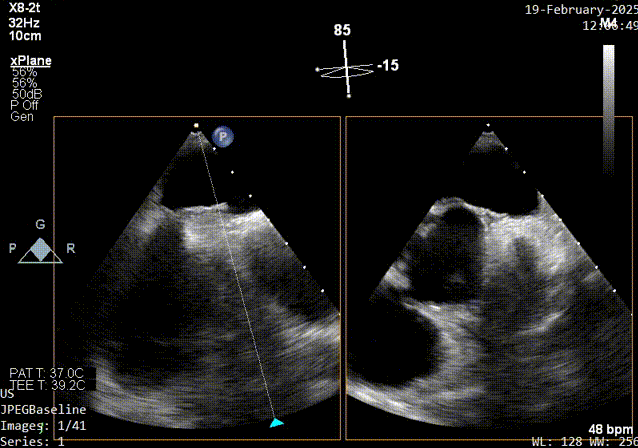

Xplane超声影像

经食道超声:房间隔卵阙窝边缘见卵圆瓣闭合不佳,可见一隧道样缝隙,长约16mm,左房面约1.6mm,右房出口约1.0-2.3mm,X-plane短轴切面而测得宽度约10mm,CDFI可在该处探及左向右过血流。原发隔卵圆瓣厚约1.3mm,继发隔厚度约4.4mm,右房面出口距主动脉根部约7mm,距上腔静脉入口约19mm。